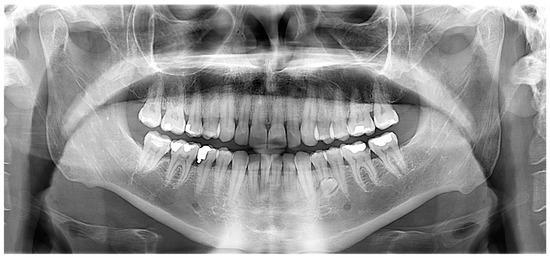

2.2. Case 2

Case 2 Presentation